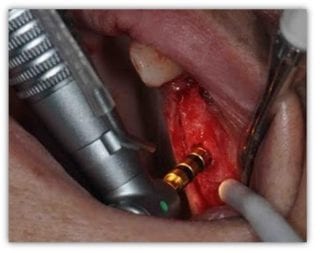

Medicul implantolog va realiza anestezia zonei şi va introduce implantul în os după care acesta va fi acoperit de gingie. Se va realiza o sutura a gingiei cu fire de sutura care vi ulteior indeparatat dupa 10 zile cand gingia se va vindeca.